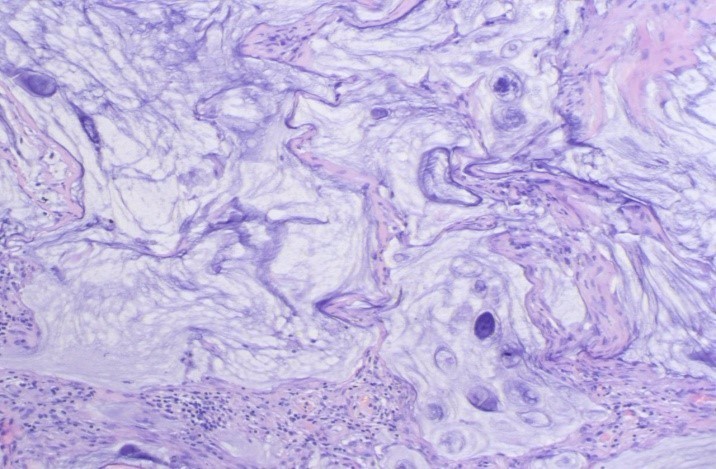

腹腔镜下观察:肝脏、脾脏、全部结肠和系膜、腹主动脉旁、乙状结肠系膜根部、盆腔侧壁无肿大淋巴结。可见大网膜形态异常,挛缩呈饼状,表面大量清亮滤泡,小肠轻度充血,肠间隙见大量纤维性渗出。经脐下纵行切口抬起大网膜,弯钳阻断大网膜组织内血管,切取约3 cm×3 cm大小网膜组织送检。病理诊断结果:(大网膜结节)大网膜弥漫黏液湖样结节,局灶见黏液上皮及异性黏液细胞,形态倾向浸润性或转移性黏液性肿瘤,免疫组化:villin(-)AE1/3(+)。

送上级医院会诊后回报:(大网膜结节)纤维脂肪组织中见大量黏液湖并见少量轻度异性的黏液性腺体,考虑为低级别腹膜假黏液瘤,请检查阑尾(见图4)。

图4大网膜弥漫粘液湖样结节,局灶见粘液上皮及异型粘液细胞

此患者转入上级医院行开腹探查可见大量淡血性腹水,吸净腹水后行右半结肠、大网膜切除术、清除胃周肿物术,同时术中行腹腔热灌注化疗。术后病检结果示:低级别阑尾黏液性肿瘤,累及浆膜下层;(右半)结肠及回肠浆膜下见黏液湖及轻度异型黏液腺上皮浸润,结肠切缘浆膜下见病变,回肠切缘浆膜面见无细胞黏液,肠周淋巴结未见肿瘤转移。纤维脂肪组织(大网膜饼、肝圆韧带)中见黏液湖及轻度异型黏液腺上皮浸润。符合伴发低级别腹膜假黏液瘤,来源于阑尾。